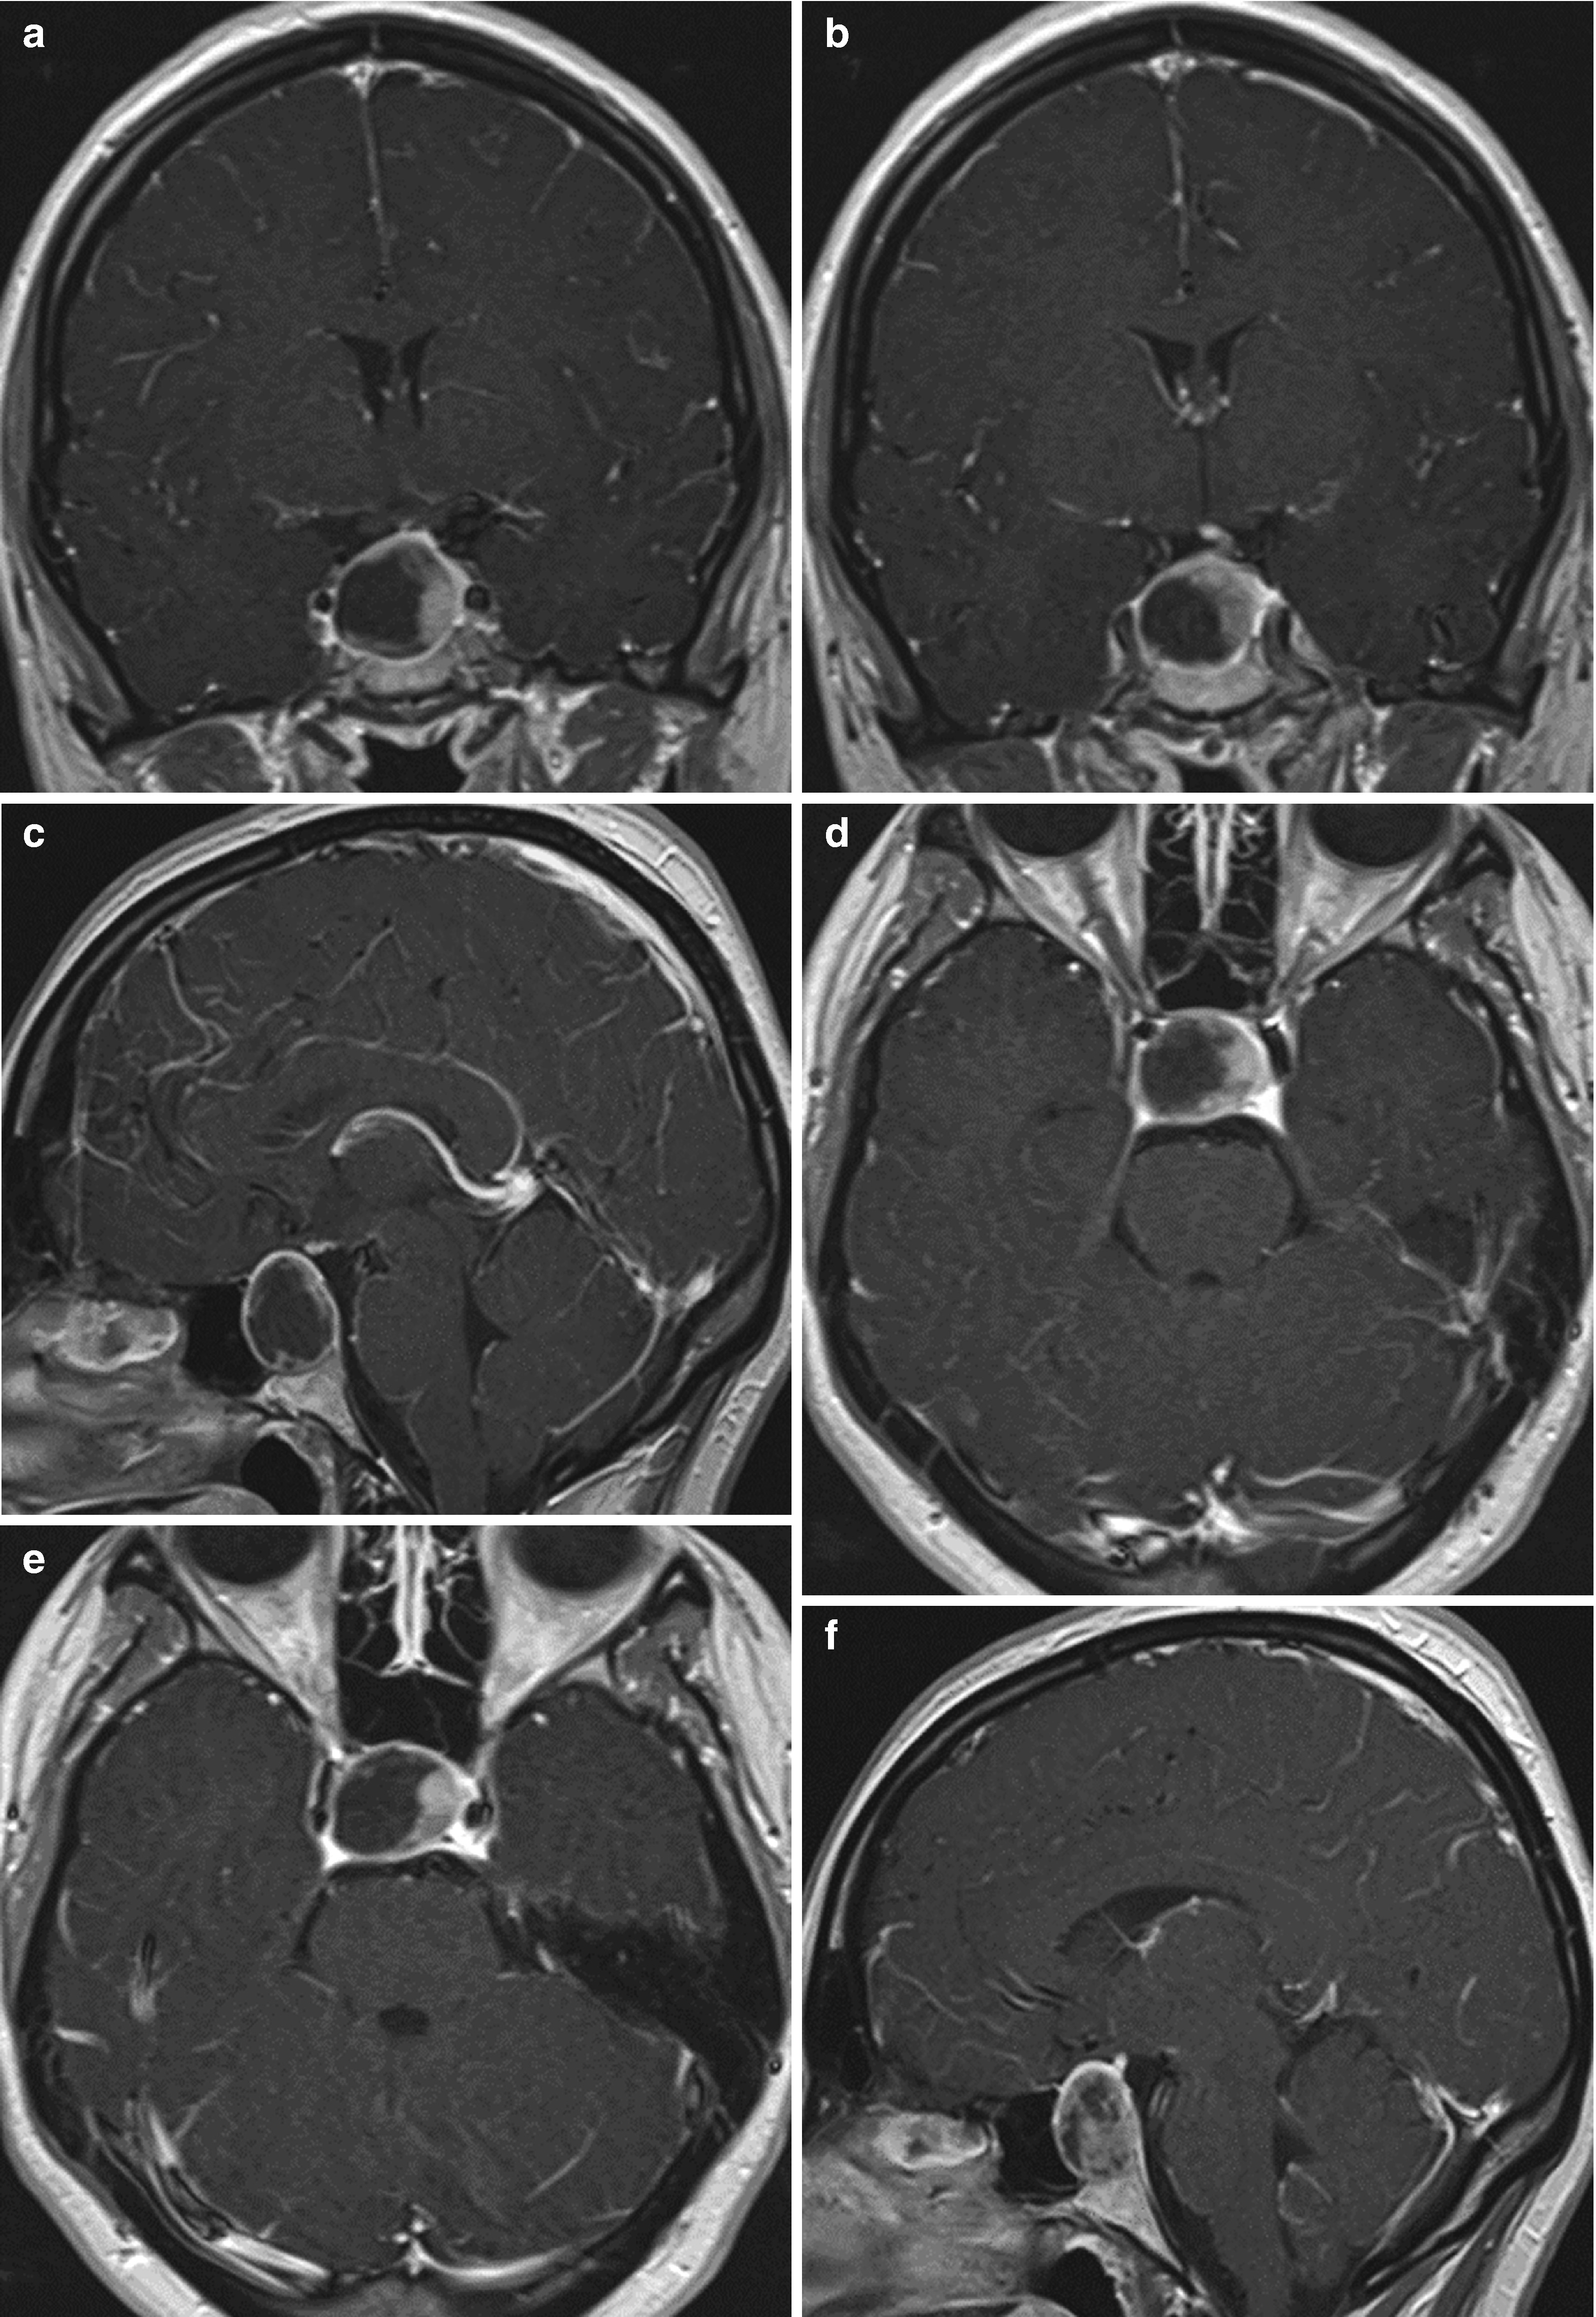

MRI T2-weighted axial image a T1-weighted post-gadolinium axial b and coronal images c demonstrate an extra-axial expansive lesion dotted circles mildly hyperintense with heterogenous contrast enhancement surrounded by cystic components. The presence of a fluid-fluid level a hypointense rim on T2-weighted images septation and an off-midline location were more common with pituitary adenomas whereas the presence of an intracystic nodule was more common with Rathke cleft cysts.

Multiple logistic regression analysis showed that cystic pituitary adenomas and Rathke cleft. MRI is superior in most cases in which differentiation of soft tissues is necessary. A cystic hygroma also known as a cystic lymphangioma is a benign fluid-filled sac caused by a malformation of the lymphatic system. Quantitative parameters of magnetic resonance imaging cannot predict human epidermal growth factor receptor 2 HER2 status in rectal cancer. An MRI is usually completed to assess for tumors and a bone density test will provide information about bone strength and possible disorders eg osteopenia osteoporosis. Differential diagnosis include adenoma myelolipoma cyst lipoma pheochromocytoma adrenal cancer metastatic cancer hyperplasia and tuberculosis.

Differentiation Between Cystic Pituitary Adenomas And Rathke Cleft Cysts A Diagnostic Model Using Mri American Journal Of Neuroradiology